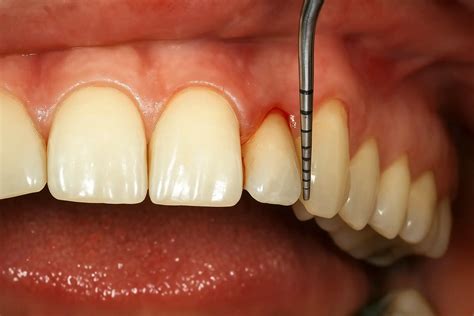

La sonda periodontal de Michigan es un instrumento esencial en la práctica odontológica, especialmente en el campo de la periodoncia. Su diseño y calibración permiten a los profesionales evaluar con precisión la salud de los tejidos periodontales, diagnosticar enfermedades y monitorear la efectividad de los tratamientos.

La sonda de Michigan-0 puede adquirirse con las marcas de Williams. Esta sonda metálica delgada, presenta las siguientes características:

- Diseño: Es delgada, con una parte activa que facilita su inserción en el surco o bolsa periodontal.

- Calibración: Posee marcas milimétricas que permiten una lectura precisa de la profundidad del surco o bolsa. La marca de 1 y 2 mm. la punta.

- Punta: Su extremo es romo y redondeado, diseñado para minimizar el trauma a los tejidos blandos durante el sondaje.

- Diámetro: Tiene un diámetro de 0,6 mm en los 5 mm y 0,7 mm en los 10 mm marcados.

Las marcas milimétricas en la sonda permiten medir la profundidad del surco o bolsa periodontal, así como la adaptación de los tejidos gingivales al diente. Es recomendable que sean usadas en sacos profundos.

El sondaje se realiza introduciendo suavemente la sonda en el surco o bolsa periodontal, siguiendo la anatomía del diente. La presión debe ser controlada (aproximadamente 25 gramos) para evitar falsas lecturas y trauma a los tejidos.

La sonda se introduce en posición recta una vez que se removía del saco. Con la ayuda de una sonda periodontal, se pueden identificar áreas de penetración más profundas y determinar diferente profundidad de la bolsa/saco periodontal.

- Medición: Observar la marca milimétrica que coincide con el margen gingival para determinar la profundidad.